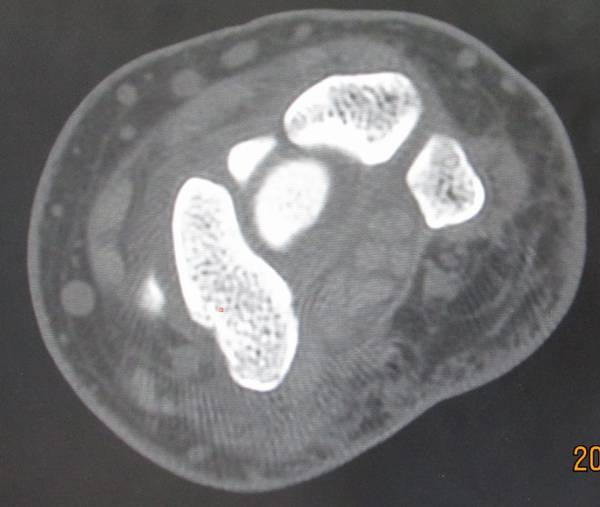

今天去ct室拍了一组舟骨骨图片

在机房看的动态的图像,想怎么看就怎么看

随便转

对骨质结构情况一目了然

太清楚了

4.png

2.png

1.png

3.png